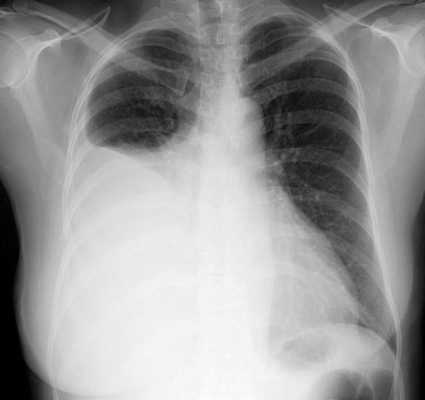

До обследования всем больным показано проведение электрокардиограммы, оценка дыхательных функций, определение статуса свертывания крови, а также рентгенограммы органов грудной клетки. Подобное предварительное исследование направлено на выявление факторов риска, способных привести к осложнению основной процедуры. Например, плохая свертываемость крови может стать причиной развития длительного кровотечения при торакоскопии.